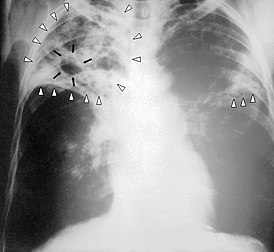

Ангелика Хоффман, из Университета Гейдельберга, Германия и коллег контролировала эволюцию ECM-связанного жидкого увеличения мозга (названный отеком, условие, которое в конечном счете приводит к набуханию головного мозга) у живых мышей, используя высоко-полевую магнитно-резонансную томографию (MRI) с цело-мозговым освещением. …